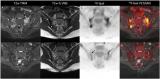

镥177-TBM精准靶向治疗为骨转移患者带来生的希望,治疗方法获得国际认可

核医学技术在骨转移瘤的早期诊断和放射性核素靶向治疗中起着关键作用。 2023-02-22 核医学放射性核素镥-177核医药靶向治疗